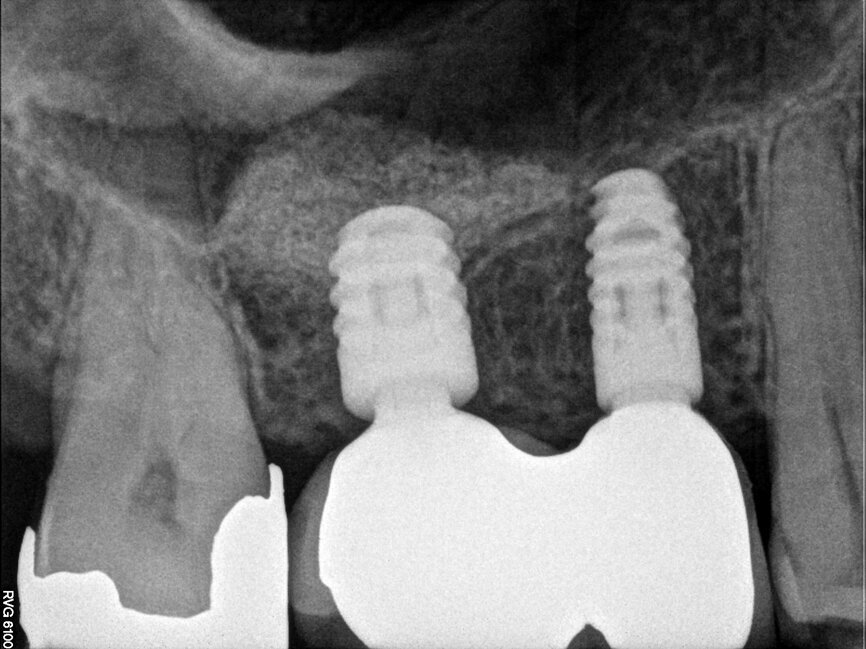

The scan was taken with a Morita 3-D CBCT system, which provides high definition, distortion-free images for accurate diagnosis and planning. Radiographic and CBCT examination revealed approximately 9 mm of bone depth, from the crest of the ridge to the floor of the maxillary antrum, in the upper right second premolar site, and no more than 5 mm bone depth in the first molar site. Planning took place immediately after the scan, with the patient present, so she could see the proposed treatment on the Navident software. She felt reassured by the care being taken to achieve optimum implant positioning, with minimal risk of potential complications, and was extremely impressed with the technology.

A 3.5 mm diameter and 8 mm length Dentsply Ankylos C/X implant was placed 1 mm subcrestally in the upper right second premolar site. A guide pin was placed in the upper right first molar site to check the depth and alignment (Fig. 11). The NaviStent was removed and the site was prepared for the sinus lift osteotome (Figs. 12 and 13). The osteotome was tapped gently with a surgical mallet until the remaining thin layer of bone infractured and was elevated (Fig. 14). The Schneiderian membrane was carefully raised through manipulation with the osteotome and a heterogeneous bovine bone graft material (Bio-Oss, Geistlich) was introduced into the implant site (Fig. 15). A 4.5 mm diameter and 6.6 mm length Ankylos C/X implant was then placed 1 mm subcrestally (Figs. 16 and 17). Both implants had good primary stability on placement. Ankylos Balance posterior sulcus formers were fitted, without the need for additional closure with sutures (Fig. 18).

Navident was used to guide the implant site preparation dynamically, to ensure implants were placed in the pre-determined position without the need for a static drilling guide. This facilitated placement of the implants in the optimum amount of bone without inadvertent damage to the maxillary sinus membrane. It also ensured that their alignment made future impression taking and restoration straightforward. The ability to watch the drill virtually on the CBCT scan, as the implant sites were prepared, allowed the exact point at which to cease vertical drilling to be judged visually.